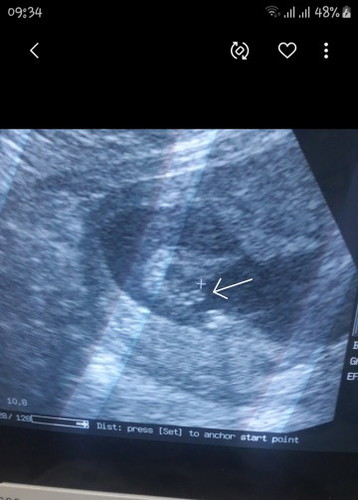

อัลตร้าซาวด์ตอน15วีคหมอบอก ผช.พอมา17วีคบอกค่อนข้างจะเป็น ผญ.พอขยับเครื่องซาวด์ไปมาบอก ผช. อิแม่นี่งง แม่ๆคนไหนเป็นเหมือนเราบ้างค่ะ รูปซาวด์ตอน15 w

รออวัยวะน้องโตกว่านี้อีกหน่อยจ้าแม่

ปกติค่ะ 15 วีคยังไม่ชัด อยากชัวๆ 20 วีคขึ้นไปค่ะ